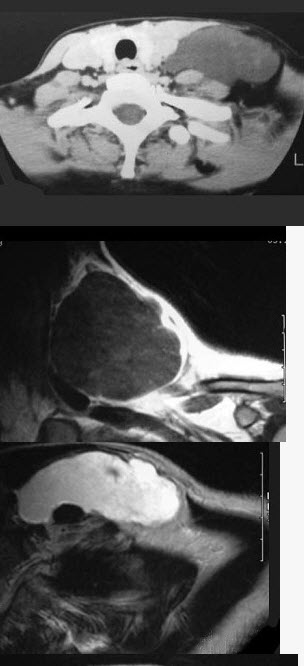

37岁女性,左侧颈部肿块渐进性增大,无压痛,局部皮温不高,CT、MRI扫描如图所示,请选择正确的描述或诊断()。

A、CT发现左侧颈后三角区可见低密度肿块影

B、增强扫描未见强化

C、MRI的T

1

WI呈低信号

D、MRI的T

2

WI呈高信号,其内可见分隔

E、考虑为淋巴管囊肿

A,B,C,D,E